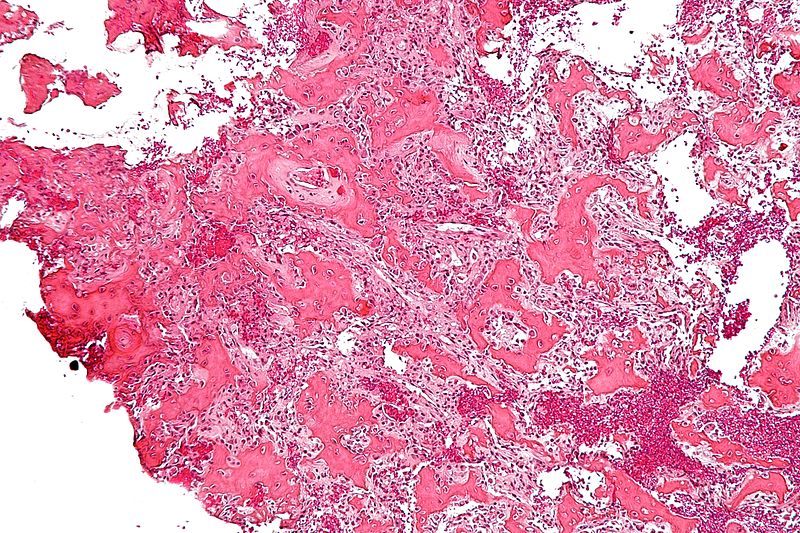

Paget Disease of the Bone

Paget disease of the bone is due to the imbalance between osteoclast and osteoblast function.

Paget disease of the bone often manifests in late adulthood with an average age of more than 60-years-old.

The cause of Paget disease of the bone is unknown, but it might be viral.

One or more bones are involved in a localized process that does not affect the entire skeleton.

There are three stages of Paget disease of the bone which include:

- Osteoclastic

- Mixed osteoblastic-osteoclastic

- Osteoblastic

The end consequence of Paget disease of the bone is bone that is dense, sclerotic, and brittle.

Histology of Paget disease of the bone reveals a mosaic pattern of lamellar bone.